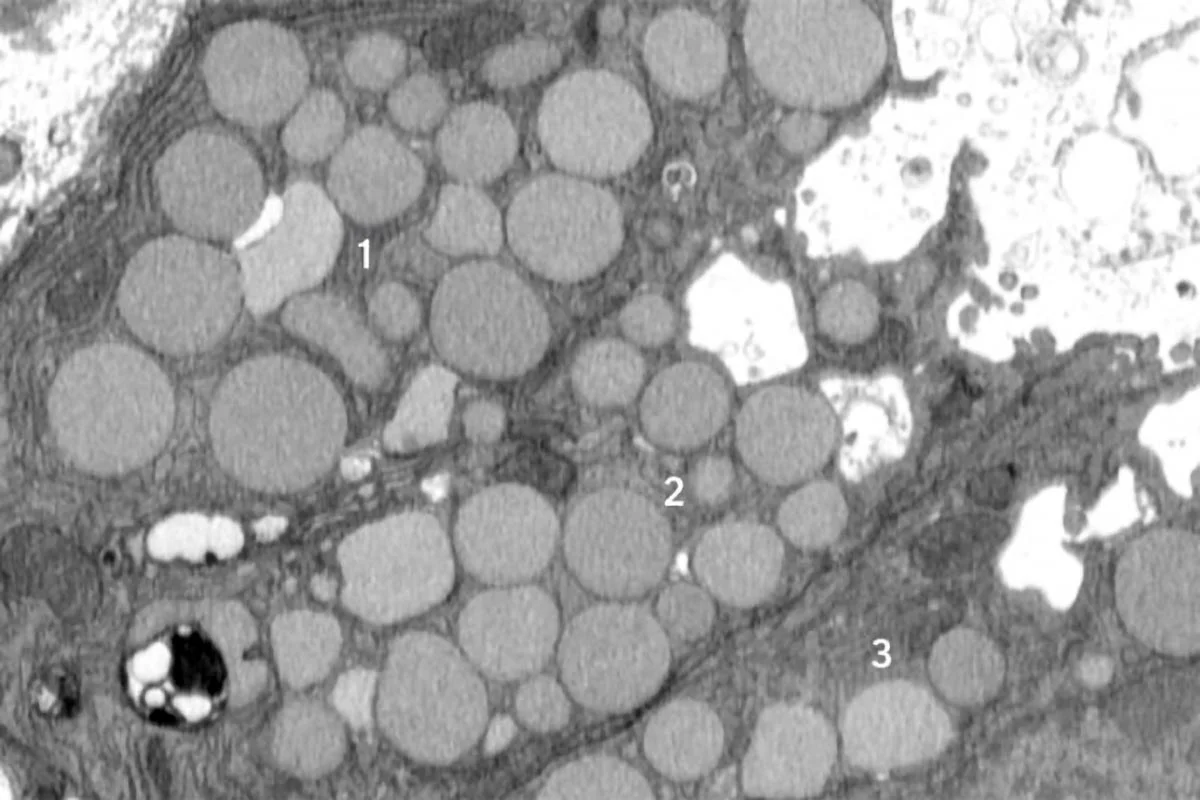

Scientists discovered a new cellular process called cathartocytosis, where injured cells rapidly purge waste to revert to a stem cell-like state for quick healing, but this process may also increase the risk of chronic inflammation and cancer, especially in the context of stomach injury and infections like H. pylori.